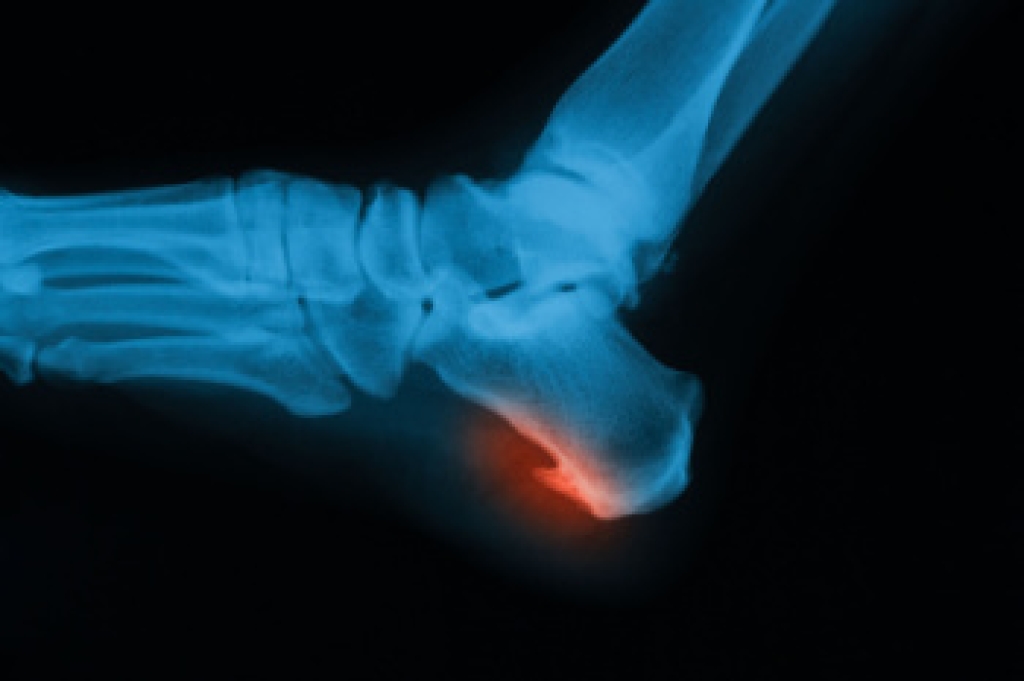

- Pain around the heel or arch area

- Swelling around the inside of the ankle